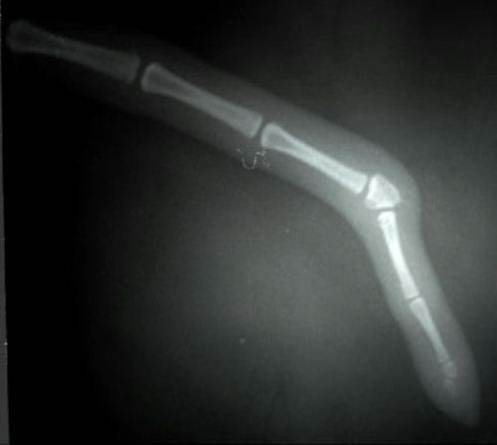

Пальця

Переломи пальців можливі, але вкрай рідко це входить у сферу інтересу хірурга. Такі пошкодження мало впливають на опороздатність. З цієї причини вони нечасто є причиною звернення в клініку.

Ще рідше можуть бути прийняті рішення щодо відновлювально-реконструктивної хірургії.

Зазвичай подібні травми підлягають самостійному загоєнню, на відміну від ушкоджень на сегмент вище. Переломи п’яти або плесна зазвичай вимагають хірургічної стабілізації. У цих випадках використовують комбінацію інтрамедулярної і зовнішньої стабілізації, оскільки інші методи фіксації в цій ділянці зазвичай малозастосовні.